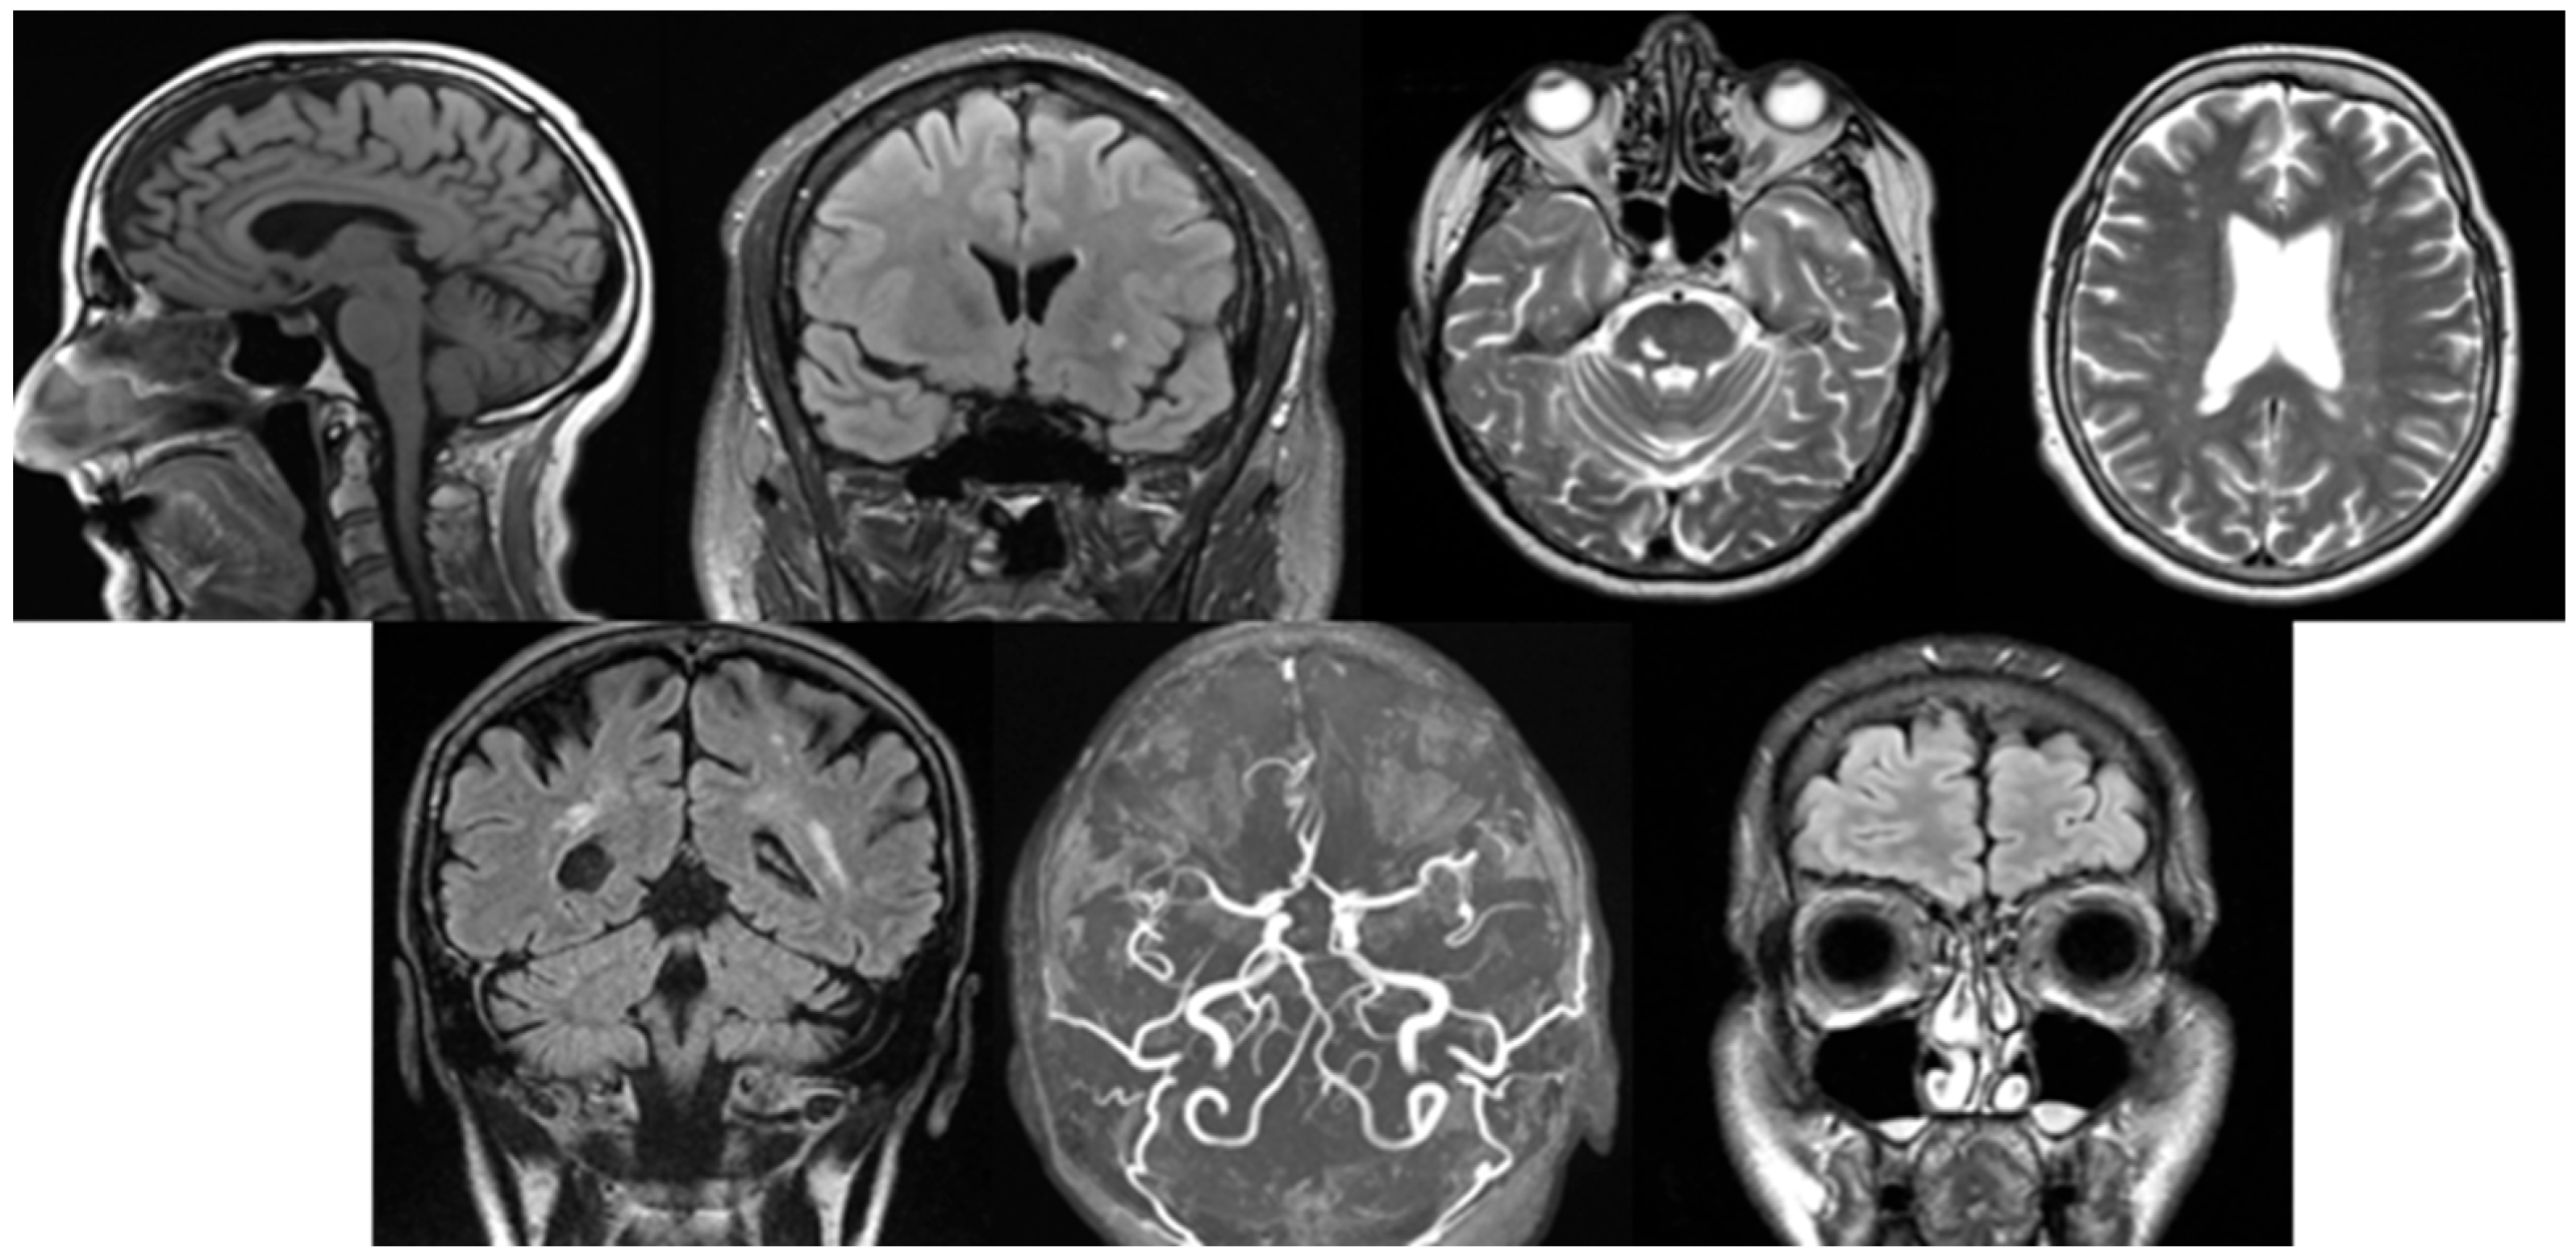

The primary outcomes are the structural changes described during MRI. Throughout the study, all findings were systematically evaluated by a neuroradiologist. To diagnose various pathologies, neurologists in Hungary apply local professional guidelines and the recommendations of the National Health Professional College. The most common pathologies were diagnosed based on the following criteria (Figure 1).

• Cortical atrophy: The Scheltens scale aids in the standardized grading of atrophy severity. It is characterized by a reduction in cortical thickness, widening of the sulci, and dilation of the ventricular system, particularly the lateral ventricles. These changes are typically observed on T1-weighted and FLAIR images, where thinning of the cortical structures is evident [10].

• White matter lesions: The Fazekas scale and the STRIVE (Standards for Reporting Vascular Changes on Neuroimaging) criteria are the most commonly used standards. White matter lesions are identified on FLAIR and T2-weighted images as bright (hyperintense) areas located in the periventricular or deep white matter. These may appear as discrete spots or confluent regions, typically indicating small vessel disease [11].

• Vascular lesions: In Hungary, the European Stroke Organization Guidelines serve as the primary reference. MR angiography is routinely used to assist in the diagnosis of vascular abnormalities. On DWI, acute ischemic lesions appear as hyperintense signals. T1/T2-weighted and MRA (Magnetic Resonance Aniography) images can identify stenosis, occlusions, or vascular wall abnormalities. In cases of haemorrhage, hemosiderin deposits can be detected using SWI techniques [12].

• Lacunar lesions: The STRIVE criteria assist in identifying these lesions. They are characterized by small (<15 mm) round or oval hyperintense areas on T2-weighted/FLAIR images. Common locations include the thalamus, basal ganglia, and internal capsule. On T1-weighted images, they appear as hypointense signals [11].

• Vascular encephalopathy: The Hungarian Stroke Guidelines and the recommendations of the MSKT (Hungarian Stroke Consensus Council), along with the application of the Fazekas scale, are essential for evaluation. Diffuse white matter hyperintensities are observed on FLAIR images. Subcortical infarcts, dilated perivascular spaces, or signs of microvascular disease may also be present. Cortical and subcortical atrophy is frequently associated with ventricular enlargement [13].

• Circle of Willis variation: The evaluation of the Circle of Willis focuses on assessing its completeness, anatomical variations, and flow characteristics. TOF-MRA is commonly used for visualization, allowing the detection of stenosis, occlusion, aneurysms, and collateral flow patterns. Variations or abnormalities are identified based on flow signal uniformity and vessel connections [14].

• Sinusitis: The ACR (American College of Radiology) Appropriateness Criteria and the Lund-Mackay scoring system are utilized. Sinus opacification, mucosal thickening, or fluid levels are identified on T2-weighted images. In acute inflammation, high-intensity signals and fluid levels are observed on T2. In chronic sinusitis, findings include thickened bony walls, fibrosis, or the presence of mucoceles [15].

Figure 1. From left to right in the first row are cortical atrophy (sagittal T1-weighted, cortical thickness and widening of the sulci), white matter lesion (coronal FLAIR, hyperintense periventricular changes), vascular lesions (axial T2-weighted, focal hyperintensity), and lacunar lesion (axial T2-weighted, hyperintense deep white matter changes), and in the second row are vascular encephalopathy (coronal FLAIR, diffuse white matter hyperintensities), circle of Willis variation (axial TOF-MRA, anatomical variation in the arterial configuration), sinusitis (coronal FLAIR, mucosal thickening and sinus opacification).